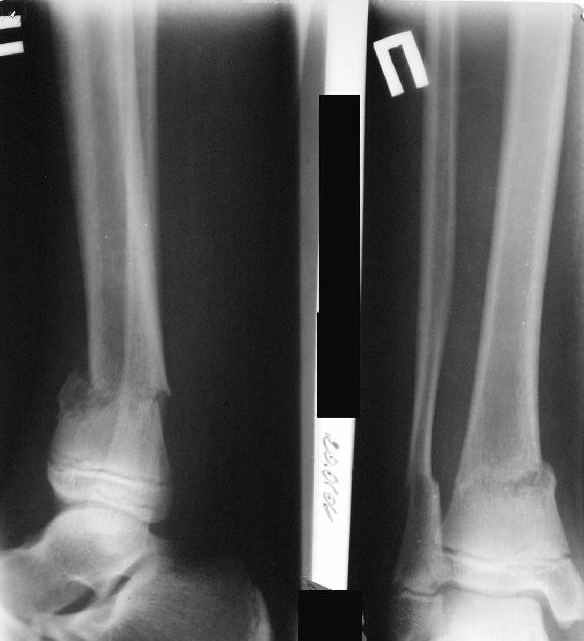

Ребенок 12 лет, поступил после падения с высоты примерно 2,5м.

Перелом костей н\3 правой голени со смещением. Перелом большеберцовой кости можно охарактеризовать как компрессионно-оскольчатый.

Скелетное вытяжение за пяточную кость.

Формирование некроза кожи по задней поверхности н\3 голени~ 1 %, вторичное заживление, кожная пластика. Нейропатия м\берцового нерва (отсутствие активного разгибания 1 пальца) На вытяжении около 8 нед, в дальнейшем в гипсовых повязках ~ 8 мес.

В январе 2005: варусная деформация н\3 голени, болевой с-м, комбинированная контрактура г\стопного сустава, нейропатия м\берцового нерва сохраняется слабость разгибания 1 пальца.

Так как речь зашла непосредственно о травме, см этапные

снимки. Как все было

Первичные

Вытяжение